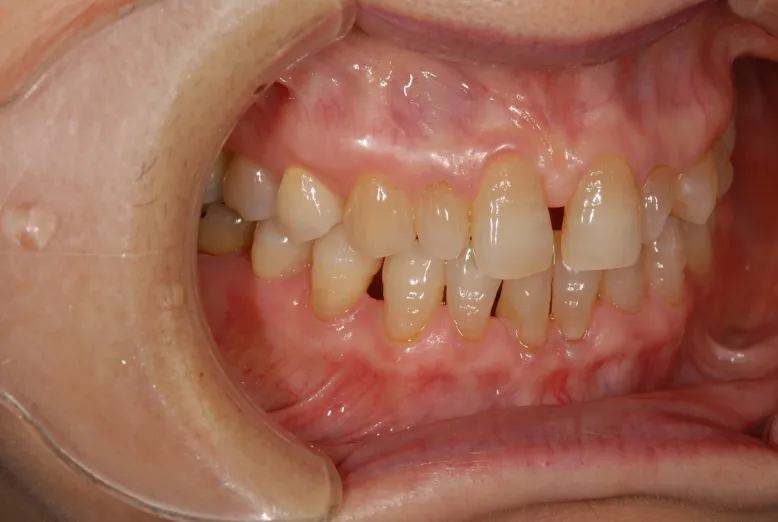

初診

歯石除去で来院されました。

除去後、話を聞くと上顎の前歯の歯と歯の間が離れていることが

以前より気になっていると仰られ、治療計画を立案。

口腔内写真の撮影

残っている歯の問題点などを解析

顔全体・口元の写真を解析

前方・口元

側方・口元

口腔内の分析・治療計画

さまざまな方向性から、歯のバランスや問題点を解析。

治療計画の立案を行います。